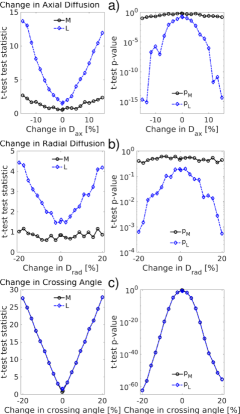

Figure 4 looks at the detectability of a broader range of changes of (Fig. 4a), (Fig. 4b) and crossing angle (Fig. 4c) between groups of simulated ODFs. Similarly, figure S1 studies the detectability of changes in number of fibers (Fig. S1a,b) and relative fiber weights (Fig. S1c). The left columns of Figure 4 and S1 plot the t-test test statistic and the right columns the t-test p-value. Changes in , and relative weight, which create more subtle differences in the ODF peaks, are better detected by analyzing the PC-scores of versus . Larger changes in the ODF, such as a shift in the ODF peak orientation by changing the crossing angle or adding fibers to the ODF, are detected equally well by both approaches. Note that there are almost linear relationships between the test statistics and the changes in diffusion parameters (Fig. 4, S1, left column).